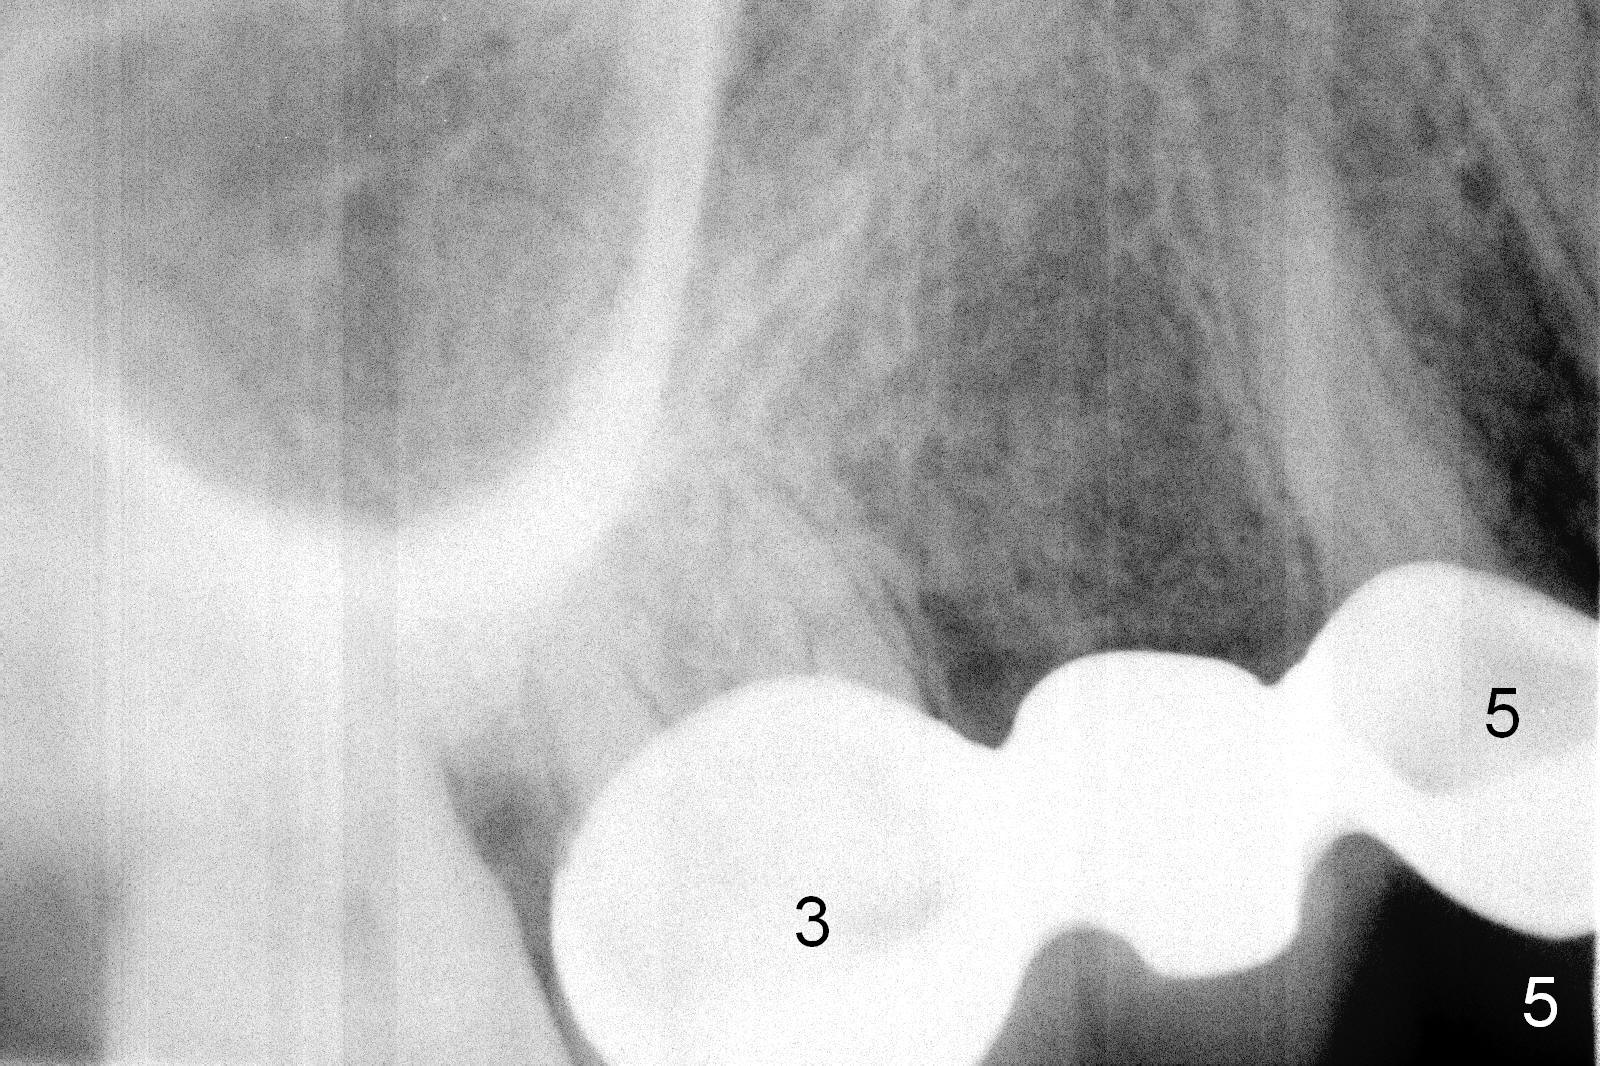

Ms. Li, a 34-year-old lady, had the upper right fixed partial denture made by an unlicensed dentist in California 10 years ago (Fig.1: #3-5). The gingival margin palatal to the retainers is erythematous (Fig.1 arrows). The patient's chief complaint is gum bleeding. The retainer at #3 is over-contoured buccopalatally (Fig.1, as compared to #14 in Fig.2), while the one at #5 is over-contoured buccopalatally and mesiodistally (compare to #12 in Fig.2). Panoramic X-ray (Fig.3), bitewing (Fig.4) and periapical film (Fig.5) all confirm that the bridge is over-contoured and that the retainers #3 and 5 have open margin (Fig.4 arrowheads). To improve oral hygiene and save the abutment teeth #3 and 5, it is in the patient's best interest to remove the bridge, place an implant at #4 and fabricate single-unit crowns at #3 and 5. Three to four months later, pyogenic granuloma develops between #4 and 5 (Fig.6 *) with generalized gingival erythema apically. The pontic at #4 and the retainer at #5 are to be removed first. An implant will be placed at #4 (Fig.7) with conjoined provisional at #4 and 5. The initial depth of osteotomy is 13 mm with Sinus Master Kit.